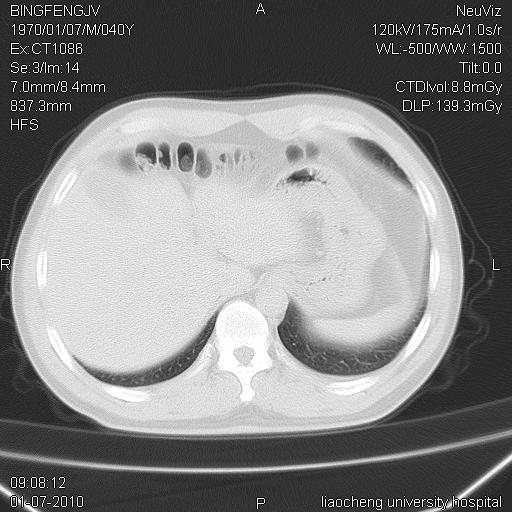

标题: CT23764B:男 40 肺部CT

治疗2周后

炎症性病灶,继发性改变。

考虑左肺上叶近胸膜下炎症并肺气囊形成。

炎症,大部吸收。